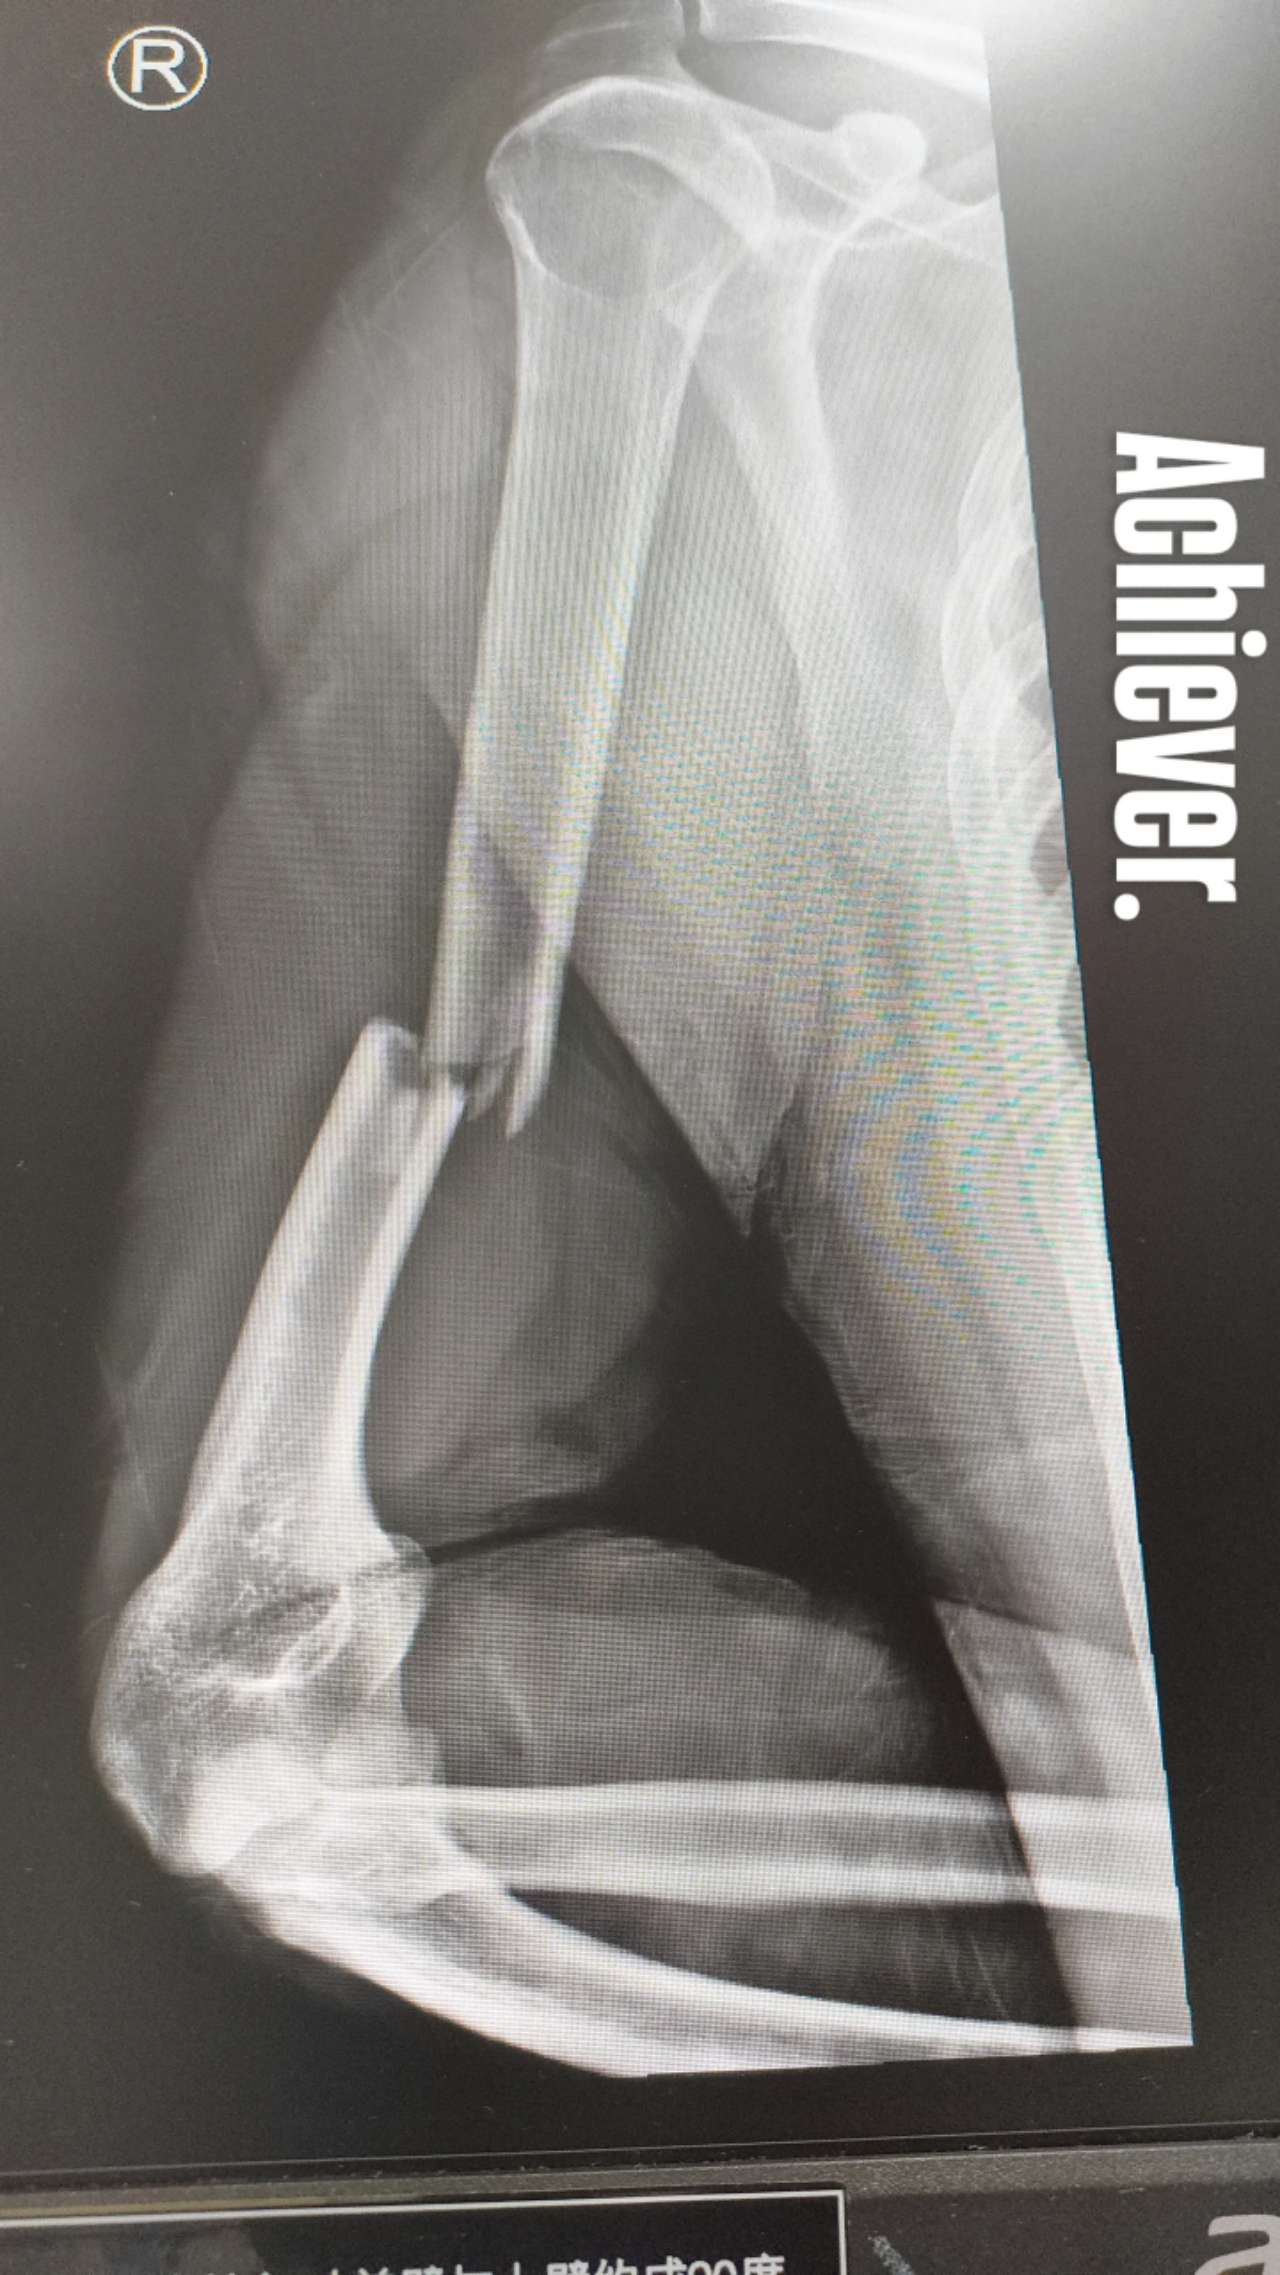

First, I’d just like to point out that whenever I set my mind to doing something, I do it to the absolute best of my ability. See X-ray for for one fine example of my work:

If this looks painful, it was. But probably not in the way you think it was painful. When I slipped, banana-peel style, on a muddy ramp and fell on my ass, I unfortunately caught myself with my right arm at a weird angle (I was wearing my backpack, too), causing what I think is called a “spiral fracture.” I immediately knew my arm was broken and, at that moment, I felt no pain, just the sickening discomfort of flaccidness from mid-humerus down. When you break your arm like this, you lose the structural integrity of the limb, which means your arm is only held together by soft tissue—bicep and my tricep—any force directed against holding the arm together is transferred from the bone to the ligaments and muscle tissue, which is a very strange, unsettling feeling indeed.

Unfortunately, the extremely thorough nurses who attended to me immediately also insisted I get an X-ray, sign some forms (mind you: I broke my right arm, aka my writing arm), pay them 5,000 yuan, and recite various identification numbers, etc. At the time, though I do not remember feeling pain, I do remember having significant difficulty remembering numbers I have memorized by heart (like my passport number, my phone number). But we got through the bureaucracy. When they printed the X-ray (above), everyone was sufficiently convinced as I was that immediate drugs were in order.